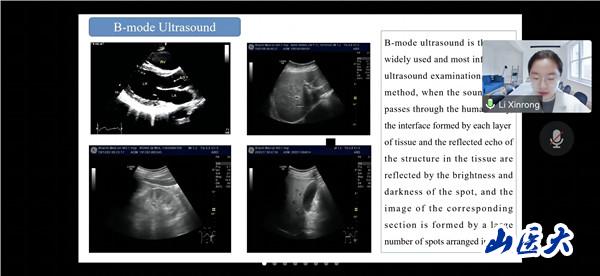

會議期間,俄羅斯沃羅涅日國立醫科大學的三名學生代表分享了超聲醫學的演進歷史,現代超聲成像技術及容積超聲診斷技術相關知識。我校第一醫院高峰、第二醫院王倩和醫學影像學院李欣榕采用豐富的病例和圖像展示了超聲影像技術在腎功能疾病、腦頸動脈疾病和甲狀腺疾病診斷和治療中的應用。與會師生認真聆聽、積極思考、踴躍提問,營造了學術思想碰撞、技術方法借鑒、疑難問題共析的濃厚氛圍。